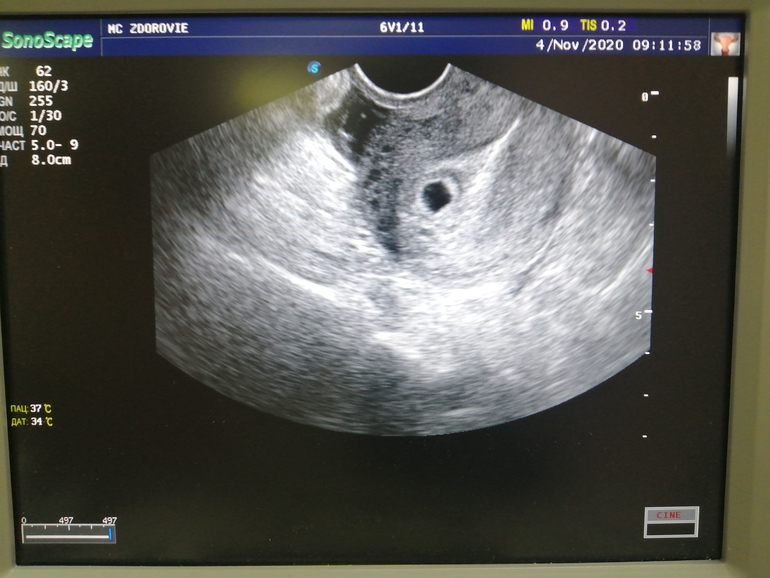

6 дней задержки, 21 ДПО

СВД 7 мм, желточный мешок есть

Длина шм 32 мм

Врач говорит, что эмбрион 2 мм, если немного датчиком покрутить и посмотреть